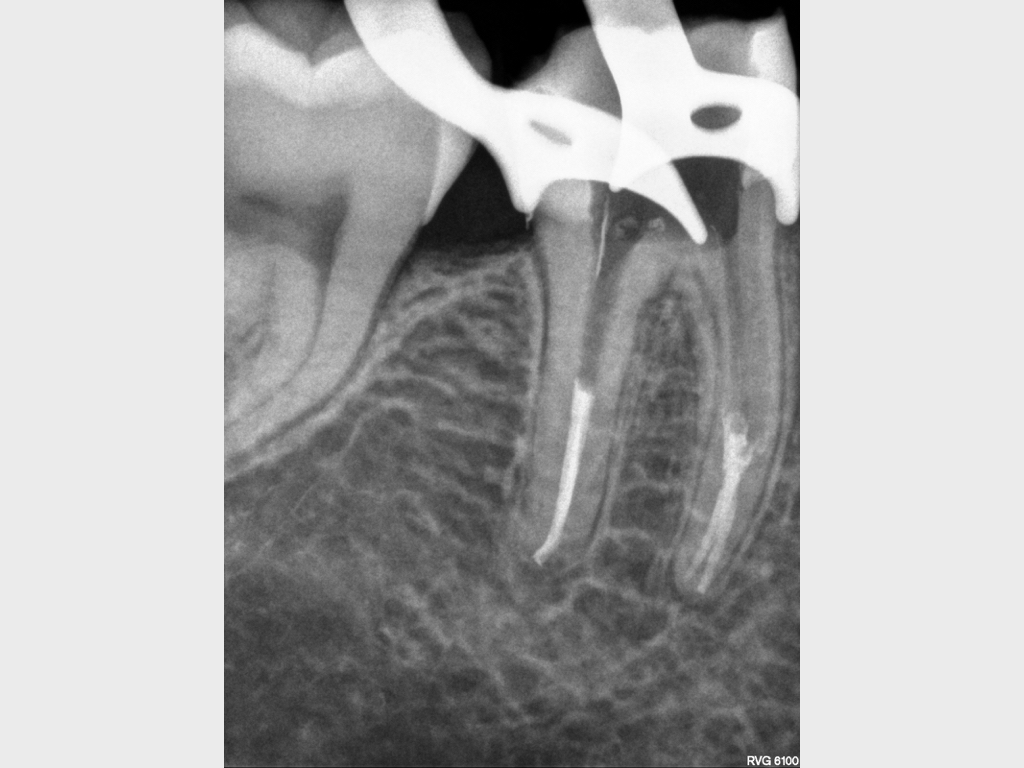

9653.006

20. Juli 2020

1024 × 768

Anamnese